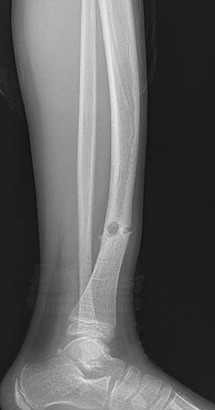

4 6 Hip Region Radiology Key